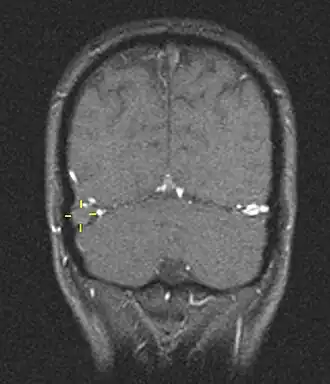

![]() Trombosis del seno venoso cerebral vista mediante resonancia magnética | ||

La trombosis del seno venoso cerebral (CVST) es la presencia de trombosis (coágulo sanguíneo) en el seno venoso dural, que recibe sangre de venas externas e internas del cerebro. Los síntomas de esta enfermedad pueden incluir dolor de cabeza, visión anormal, cualquiera de los síntomas de un accidente cerebrovascular (debilitamiento de los músculos de la cara y extremidades de una mitad del cuerpo) e infartos. El diagnóstico se realiza normalmente por tomografía axial computarizada (CT/CAT scan) o resonancia magnética (MRI) empleando el contraste radiológico para demostrar obstrucción de los senos venosos por trombos.[1]

Hay varias formas de neuroescaneo que pueden determinar la presencia de la trombosis del seno venoso cerebral. Los edemas cerebrales e infartos venosos pueden hacerse visibles en cualquier modalidad, pero para la detección del trombo sí, el tipo de escaneo más usado comúnmente son la tomografía axial computarizada (CT) y la resonancia magnética (MRI). Ambas usan varios medios de radiocontraste para elaborar un venograma y visualizar las venas en torno al cerebro.[1]

La resonancia magnética venosa emplea los mismos principios, pero la modalidad de escaneo usada es la resonancia magnética. La MRI tiene la ventaja de ser mejor a la hora de detectar peligro para el cerebro como resultado del incremento de la presión en las venas obstruidas. No obstante, este mecanismo no se encuentra disponible en muchos hospitales y su interpretación puede resultar dificultosa.[6]